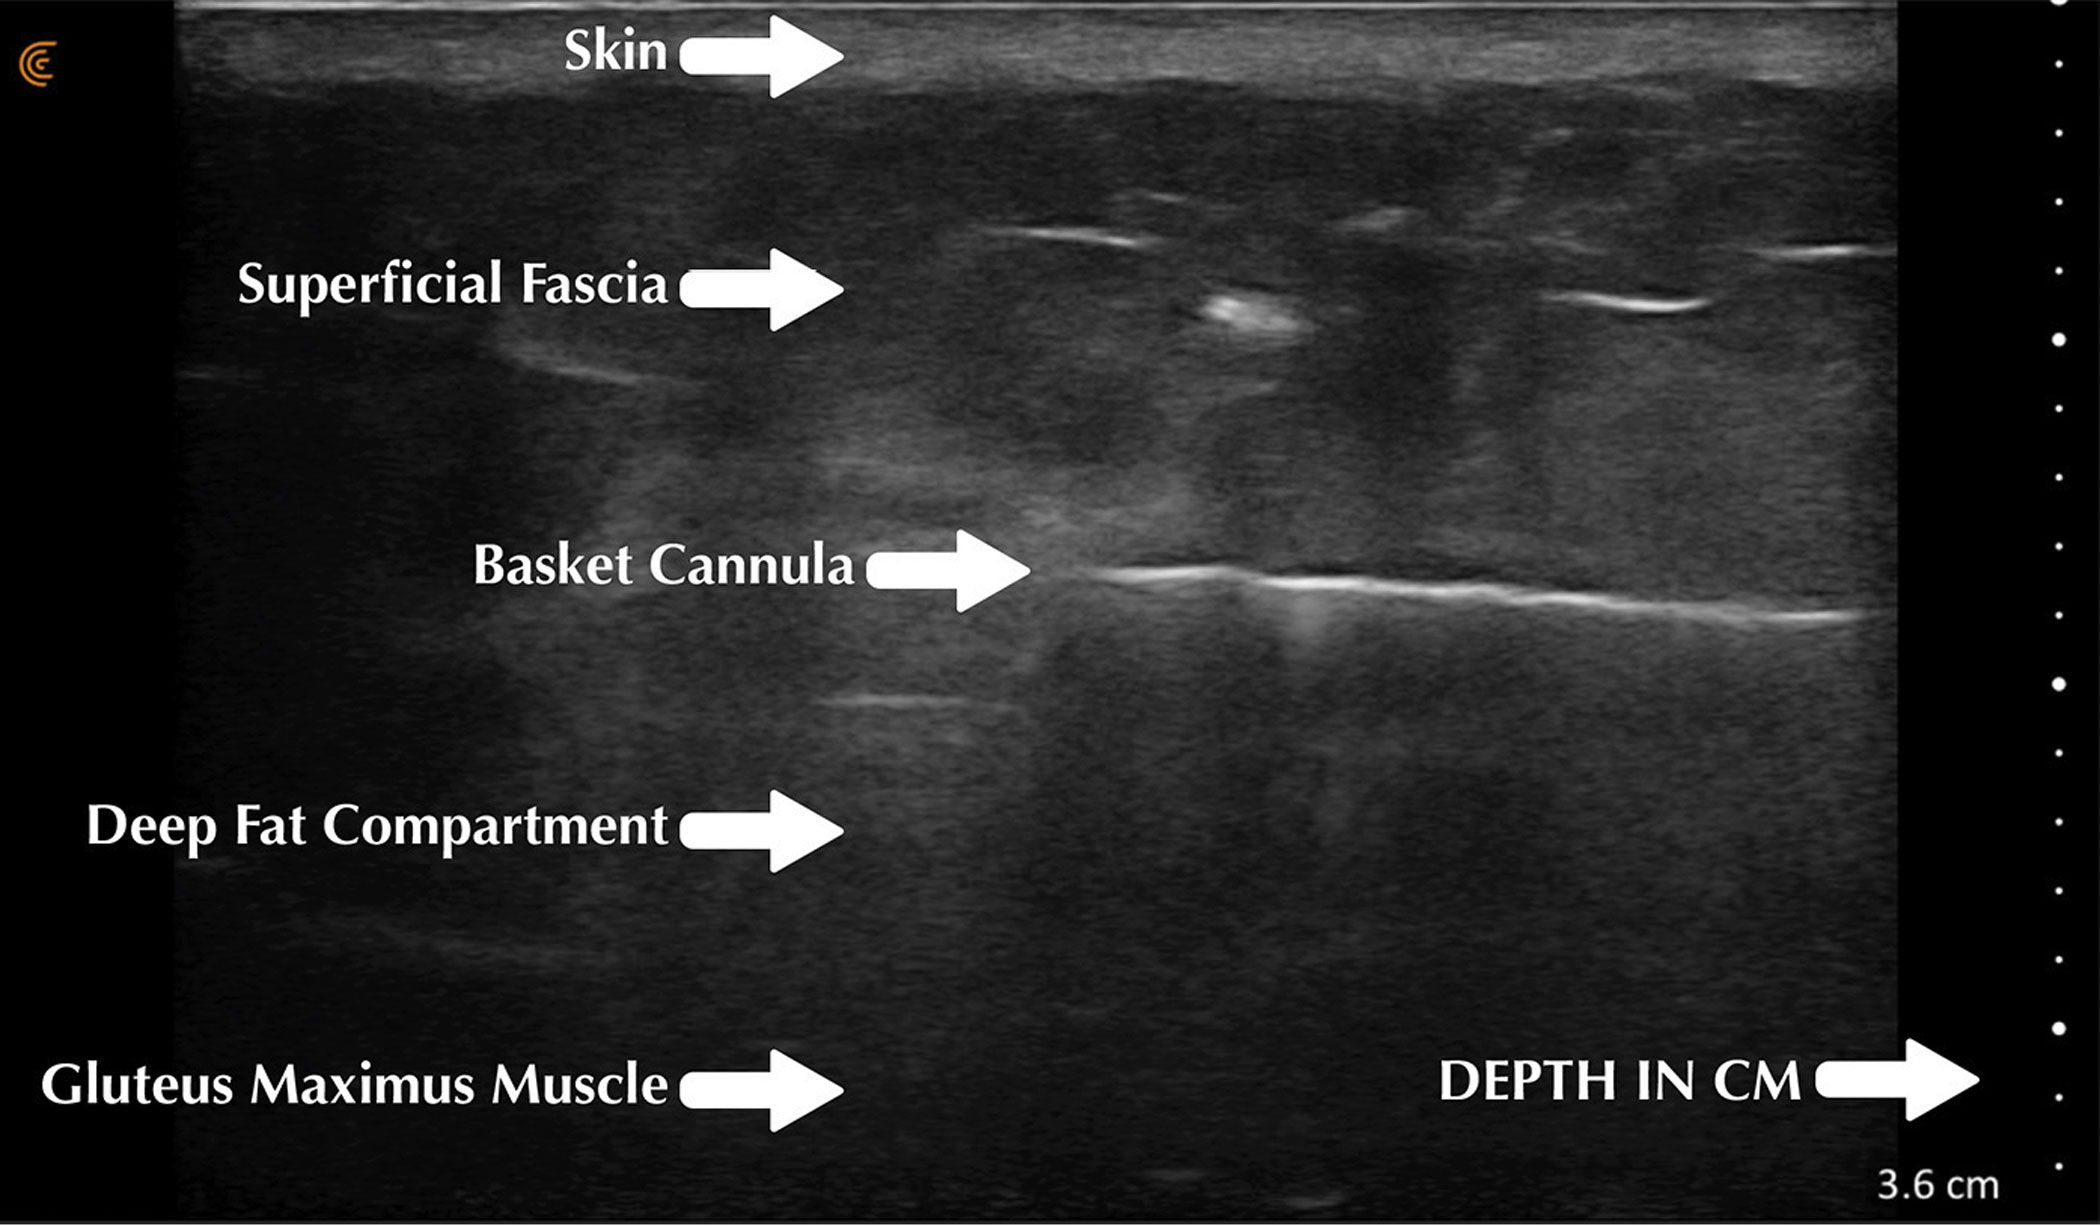

Intraoperatively, ultrasound has revolutionised the safety of gluteal fat transfer (BBL) by allowing the operating surgeon to see the exact plane where the fat is being placed in real time (Figure 1) - removing guesswork and keeping the cannula within the fat above the gluteus maximum muscle massively reduces the chances of fatal fat embolism as the largest veins which are greatest risk for fat embolism lie within the muscle. This has been proposed as a mandatory use in this procedure.